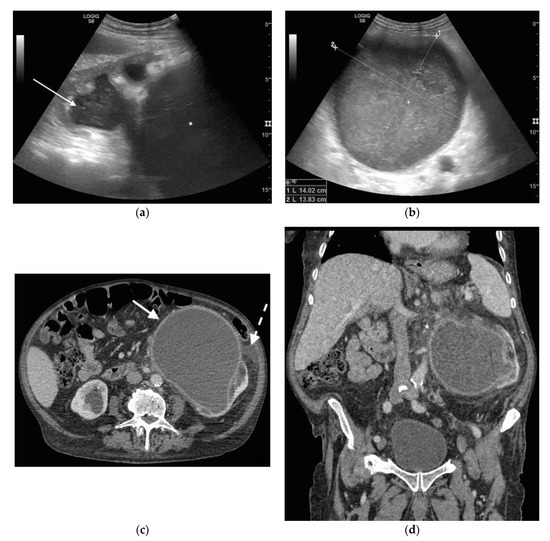

Figure 1. A 78 years old septic male patient. Ultrasound (US) longitudinal (a) and axial (b) view of the left kidney showing high-grade hydronephrosis with gross dilatation of the renal pelvis and calyces, filled by inhomogeneous urine (white arrow) and an extremely dilated inferior calyceal group filled by a huge ball of debris conglomerate (*). Axial (c) and MPR coronal Computed Tomography (CT) (d) after intravenous contrast in cortical-medullary phase, showing high grade hydronephrosis, diffuse parietal thickening of the calico-pelvic system (white arrow), fat stranding of perirenal and renal sinus fat. Small amount of free fluid is appreciated anteriorly (dashed arrow).